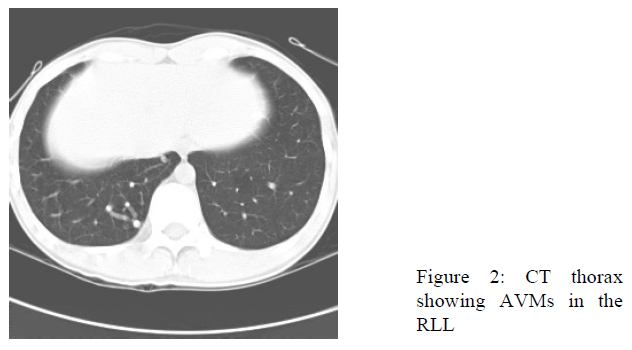

CT thorax was performed subsequently. Four arteriovenous malformations (AVMs) ranged from 0.6cm to 1.5cm were detected in right lower lobe (Fig.2). They all received single artery supply from branches of right lower lobe pulmonary artery and drained to a single vein towards right inferior pulmonary veins. This patient had no telangiectasia over face, chest and upper extremities. There was no mucosal telangiectasia. He had no epistaxis or history of gastrointestinal bleeding. He had no family history of hereditary haemorrhagic telangiectasia (HHT).